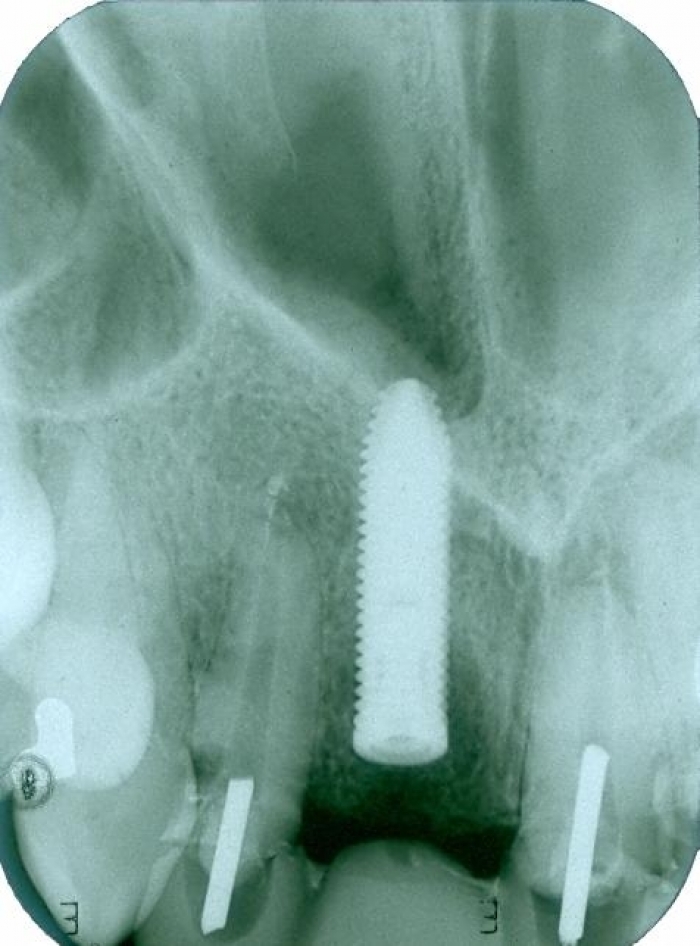

Rx dos implantes Cone Morse instalados

Rx após extração e implantes imediatos nos dentes 12 e 22